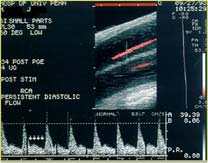

L’ecocolordoppler penieno dinamico è un’indagine ultrasuonografica che serve ad accertare le condizioni delle arterie del pene al fine di valutare se sono integre (visualizzandone il loro decorso) e se queste portano sangue ai corpi cavernosi in quantità e pressione sufficienti. Sostanzialmente è identico a quello che viene eseguito sulle arterie di altre parti del corpo con la differenza che le strutture in esame vengono stimolate con farmaci vasoattivi nella fase cosiddetta dinamica (PgE1 o cocktail di PgE1, fentolamina e papaverina). Una sonda viene appoggiata in corrispondenza delle arterie che si vogliono controllare: si hanno così delle immagini e un tracciato che ne mostrano le condizioni.

Inoltre con l’avvento della metodica “Power-Doppler”, importante evoluzione tecnica, ha assunto sempre maggiore importanza l’osservazione dell’aspetto morfologico della distribuzione vasale endocavernosa consentendo così l’individuazione di patologie ai primissimi stadi, o addirittura in fase latente, in soggetti “a rischio vascolare” (es. ipertesi arteriosi, diabetici, dislipidemici, fumatori) anche in età giovanile. L’indagine, non fastidiosa né dolorosa, è eventualmente ripetibile dopo adeguata terapia vasoattiva nei casi di disfunzione erettile prettamente vascolare.